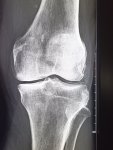

Здравствуй двачик, пишет вам простой рентгенолог из мухосранской поликлиники, сегодня я буду флексить зарплатой за ноябрь! Аж ПЯТЬДЕСЯТ ТРИ ТЫЩИ ПЕРЕВЕДУТ! С пруфом! А чего достигли вы? Ну и в доктора тож поиграем! Я буду вам картинки показывать, а вы пиздецомы находить! Найдите пиздецому на фтчк! Отчет еще по фог считать квартальный и годовой сегодня :-(